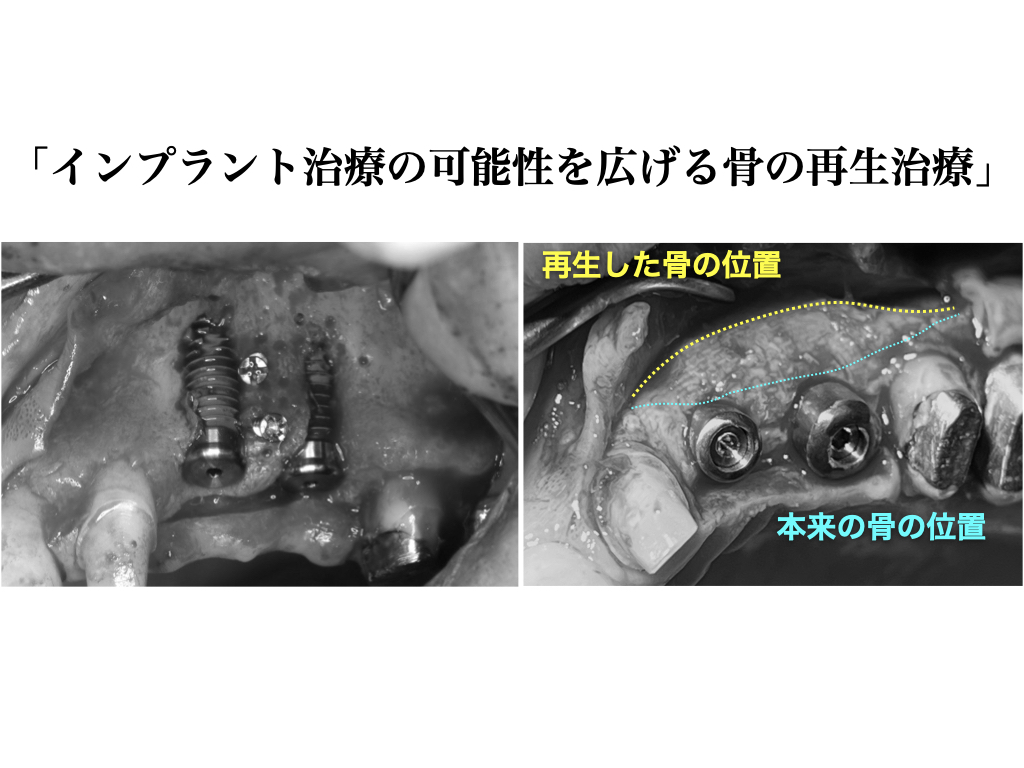

《骨の再生治療を併用したインプラント治療例》

(図説)骨幅が狭くインプラントを埋め込んだ際に、インプラントが露出している状態。この状態だとインプラントの安定性に欠けるため、骨の再生が必要である。

(図説)生体親和性の高い材料(骨補填材、吸収性遮断膜)を使用し、骨の再生治療を行った。

(図説)術後5ヶ月の状態。再生した骨によってインプラントが完全に覆われる。

インプラントが露出していた部位には、インプラントの安定に必要十分な骨が再生した。